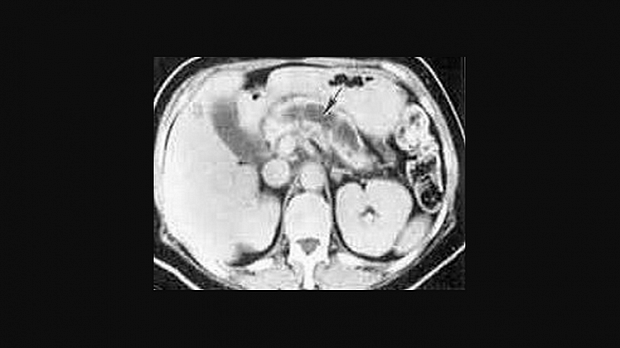

Иллюстрация №4: РХПГ при хроническом панкреатите (Изменения по типу "жемчужной нити")

Амилаза и липаза сыворотки может соответствовать норме или быть незначительно повышена. У 5-10 % пациентов с хроническим панкреатитом компрессия дистальной части общего желчного протока ведет к увеличению билирубина сыворотки и щелочной фосфотазы. Мальабсорбция жира ведет к увеличению его экскреции с калом (более 7 грамм в день). Выявление панкреатических кальцификатов при рентгенографии, УЗИ или компьютерной томографии является диагностическим критерием хронического панкреатита. Эти кальцификаты обнаруживаются в примерно 25-60 % всех случаев хронического алкогольного панкреатита и у 35-80 % пациентов с панкреатитом другой этиологии. Компьютерная томография может также выявить локальное увеличение размеров поджелудочной железы, ее атрофию, расширение панкреатического протока или псевдокисту. РХПГ является наиболее чувствительным и специфическим визуализирующим исследованием в диагностике хронического панкреатита (рис. 3).

Из-за риска развития панкреатита в результате выполнения РХПГ эта диагностическая процедура должна применяться только когда неинвазивные исследования являются малоинформативными. Новые, более современные виды исследований, как ядерно-резонансная холангиопанкреатография и эндоскопическое ультразвуковое исследование становятся все более популярными. Если с использованием всех этих визуализирующих исследований не удается подтвердить диагноз, то может быть выполнено тестирование функции поджелудочной железы со стимуляцией секретином или ХК [10]. Диагностический алгоритм приведен на рисунке 4.